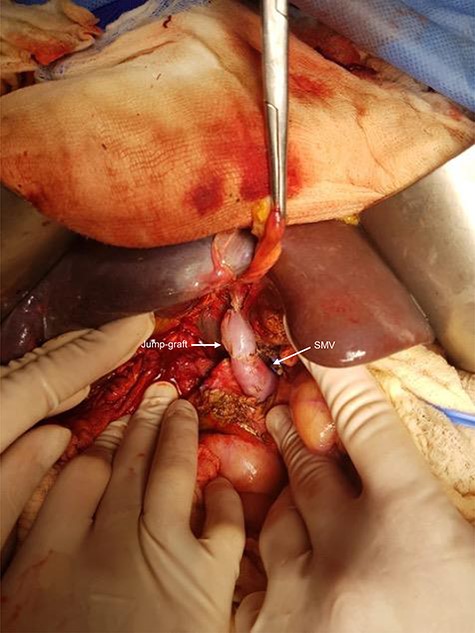

She was taken to the operating room on suspicion of an extreme VBI. Surgical findings were turbid bile peritonitis, right hepatic lobe necrosis and ischemia of the left lobe, complete resection of the common bile duct at the level of the confluence of right and left ducts (Strasberg E3), occlusion of the main portal vein (by several stitches) and a full section of the proper hepatic artery (Figs 4 and 5). The accessory left hepatic artery was not damaged. A right hepatectomy was undertaken. After portal and superior mesenteric vein thrombectomy, revascularization of the left hepatic lobe using a jump-graft (deceased donor iliac vein) from the superior mesenteric vein to the left portal branch at the Rex recessus was done. Also, a Roux-en-Y hepaticojejunostomy to the left hepatic duct was performed (Figs 6–9). Arterial and portal flow was verified with an intraoperative Doppler ultrasound before closure of the laparotomy. After surgery, the patient was shifted to the ICU.

The white arrows show the jump-graft (deceased donor iliac vein) from the superior mesenteric vein (SMV) to the left portal branch at the level of the Rex recessus.